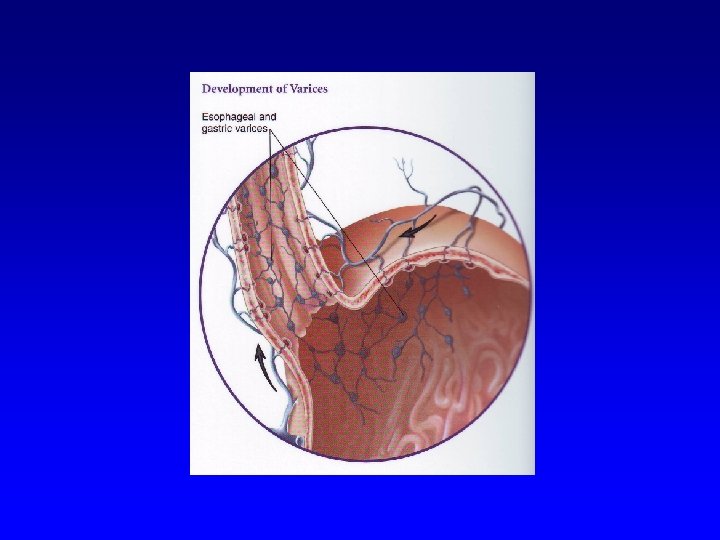

Clinical course of HEP C • • • ü ü LC in about 20 % patients with chronic HCV infection HCC annually in 1 -4 % patients with LC Progression to HCC depends on: age (more rapid progression in older persons) alcohol abuse HIV co-infection HBV co-infection